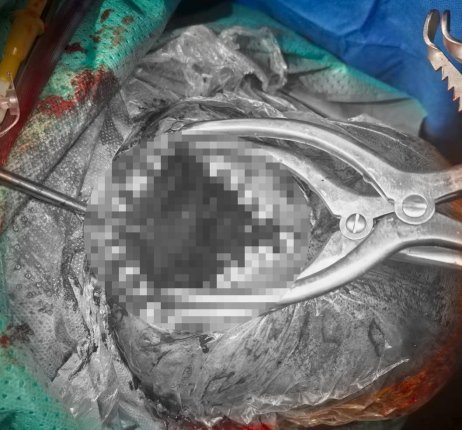

稳定后方,解除小脑压迫

手术团队率先针对枕部硬膜外血肿开展救治,采用枕部正中直切口,精细分离肌肉组织以暴露病变骨区。枕骨钻孔后,压迫小脑的硬膜外血肿被迅速且彻底清除,有效缓解颅内高压;针对术中出现的后矢状窦活动性出血,团队通过硬脑膜缝合悬吊术精准止血,为后续治疗奠定基础。

转场攻坚,处理左侧额颞部危机

复查显示,患者左侧额颞部硬膜下血肿体积显著增加,大脑受压情况加剧,生命再次受到威胁。医疗团队当机立断,立即实施第二场手术。

调整患者体位后,医生于左侧额颞顶部取大问号型切口,去除骨瓣后发现脑膜压力极高。团队精准切开脑膜,彻底清除积聚的血凝块与出血,并妥善处理撞击受损的脑组织;待颅内压力成功释放、大脑恢复正常搏动后,采用人工脑膜完成修补,确保脑部结构稳定。